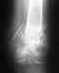

Травма получена 29 сентября 2009 в ДТП. 8 сентября проведена открытая репозиция, фиксация перелома правой локтевой кости. 30 сентября выписан из больницы с полностью свободной рукой. Через месяц вышел на работу, не испытывая никаких неприятных ощущений кроме мыслей о том что пластину надо будет когда то вынимать. 21 декабря контрольный снимок показал что пластина сломана и имеется избыточная костная мозоль, срастания кости нет. Тут же мне наложили гипс. Снимок через месяц показал отсутствие положительной динамики. 16 февраля сняли гипс, 18 февраля провели удаление пластины и остеоперфорацию зоны ложного сустава диафиза правой локтевой кости. Через 2 недели наложили гипс. 22 марта сняли гипс так как сказали что больше ходить с ним нельзя, сделали снимок на котором присутствовала положительная динамика (оссификация в мягких тканях). Назначили сделать рентген через 3 недели и разрабатывать руку(после снятия гипса она так и осталась стоять под 90 градусов). За неделю я почти разработал руку в теплой ванной, осталось примерно 15 градусов до полноценного движения руки в локтевом суставе. Вопрос:Каковы мои шансы избежать новой операции, и как правильно себя вести пока полного срастания перелома нет, но и рукой надо при этом шевелить.

Без рентгенограммы по одному перечислению событий оценить ситуацию невозможно.